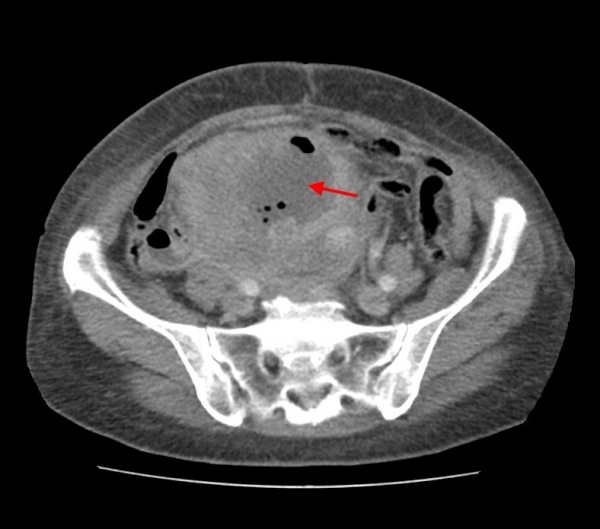

КТ живота и таза. Массивное объемное образование яичника с гиповаскулярным центром (красная стрелка), гиперваскулярной периферией (зеленая стрелка) и включениями газа (синяя стрелка). Гистологически подтвержденная гранулезоклеточная опухоль яичника.